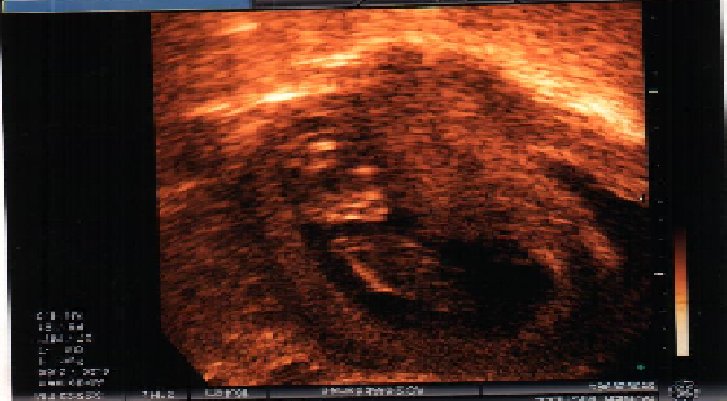

12 - 13 weeks lookin good !

12 - 13 weeks # 2 still lookin good ;)